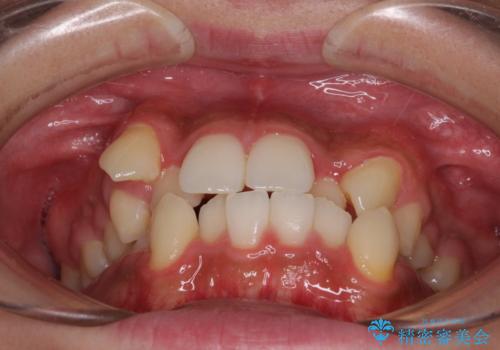

上下の八重歯とクロスバイト ワイヤー装置での抜歯矯正

- 八重歯とクロスバイトを気にして来院された患者様です。

上下ともに八重歯が顕著であり、前歯のクロスバイトがあったため、上下左右の第一小臼歯4本を抜歯し、ワイヤー装置での抜歯矯正を行うこととしました。